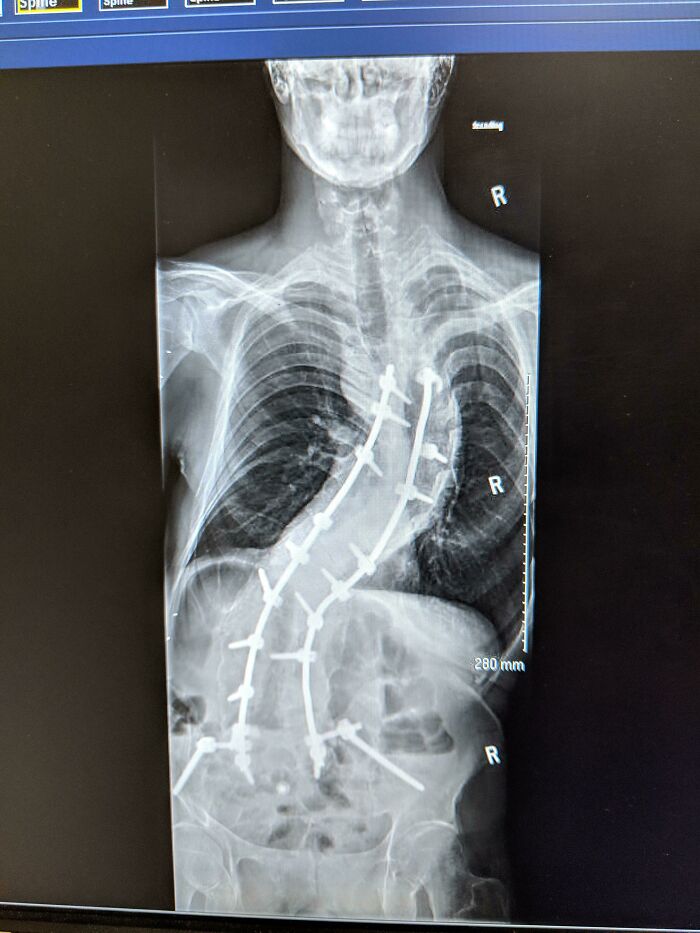

2 Years Post Op Spinal Fusion. Yeah, That's Me

Not if you have scoliosis. I have both kinds and I am post surgery since 1985. I was the first adult in the us older than 18, to have the Harrington rod type of surgery. Thank you Shriners. They did my release surgery a week before my 18th, and my rods a week after. I've had children and everything I wanted to do. It's miracle surgery.